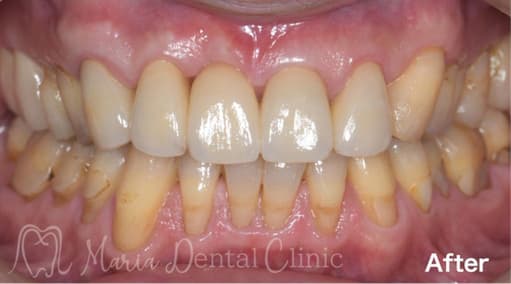

歯肉移植の症例

インプラントを守るために強い歯茎を移植(FGG)

インプラントの周りの硬い歯茎が失われた患者様に対する、歯茎再生の手術(付着歯肉を増やすための歯茎の移植)を行った症例です。

| 治療内容 | 遊離歯肉移植術(FGG) |

|---|---|

| 治療期間 | 3ヶ月(移植した歯茎が落ち着くまで) |

| 治療回数 | 1回(他、抜糸や経過観察を除く) |

| 治療費用 | 137,500円(税込) |